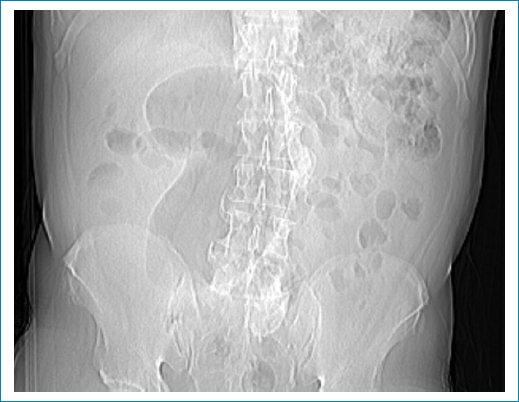

Figura 1. Radiografía de abdomen de paciente masculino de 47 años con dolor abdominal de tipo cólico de 5 días de evolución, que asocia náuseas, sin otros síntomas de jerarquía. Se observa el signo del embrión cecal en fosa ilíaca derecha, de aspecto “segmentado” por las haustras colónicas (tomada de Wismayer R4).

Según la literatura, tanto en la radiografía de abdomen como en la TC, el vólvulo cecal puede observarse en cualquier cuadrante abdominal5 (dependiendo de su movilidad) con forma de embrión, compuesto por un “polo cefálico” cecal dilatado y uno o dos “segmentos” distales, semejando el cuerpo y la cola, cuya concavidad suele apuntar hacia la derecha (Fig. 2). A diferencia del vólvulo sigmoideo, que presenta un aspecto “liso” de las paredes colónicas, las haustras cecales son visibles3, dando el aspecto lobulado a las asas distendidas (Fig. 3). En el caso de la radiografía, el signo suele asociarse también a la presencia tanto de distensión gaseosa en el íleon terminal como de ausencia de gas en la ampolla rectal.